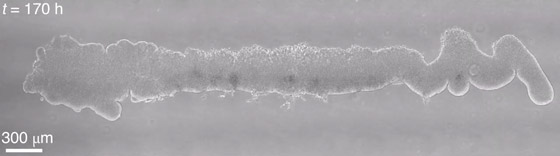

وتم إنشاء النموذج الجديد باستخدام الخلايا الجذعية البشرية متعددة القدرات، أي الخلايا التي لديها القدرة على أن تصبح أي نوع من الخلايا في الجسم. وفي البداية، حث العلماء الخلايا الجذعية لتشكل صفا يبلغ طوله نحو 4.39 سم وعرضه 0.018 سم. وكان هذا الهيكل يشبه، ولكنه لم يتطابق تماما، شكل وحجم الأنبوبة العصبية (المسؤولة عن تكوين الحبل الشوكي والمخ أثناء الأسابيع الأولى من مراحل تكوين الجنين)، والتي تكون موجودة في جنين بشري عمره 4 أسابيع.

ثم قام الفريق بعد ذلك بوضع هذا الصف من الخلايا في ما يسمى بجهاز الموائع الدقيقة الذي يحتوي على الكثير من القنوات الصغيرة. وعرّضوا الخلايا لمواد كيميائية مختلفة عبر هذه القنوات، ما دفع الخلايا إلى النمو وتشكيل بنية ثلاثية الأبعاد تشبه الجهاز العصبي المركزي المبكر. وأضاف العلماء أيضا مادة هلامية دفعت الخلايا الجذعية إلى التخصص في الخلايا التي ستشكل فيما بعد الخلايا العصبية التي ترسل الإشارات في الجهاز العصبي.

وعلى مدار 40 يوما، نظمت الخلايا الموجودة داخل العضية نفسها هياكل تشبه المراحل المبكرة من تطور الدماغ والحبل الشوكي في الجنين البشري. وشمل ذلك تكوين الهياكل المعروفة باسم الدماغ الأمامي، والدماغ المتوسط، والدماغ المؤخر، بالإضافة إلى الحبل الشوكي.